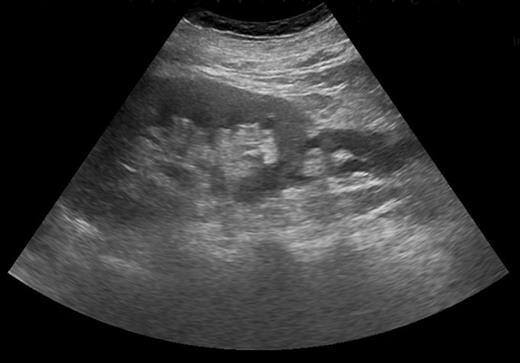

Blood tests revealed a Stage 3 acute kidney injury (baseline renal function was normal) with raised inflammatory markers and elevated PSA compared with baseline (Table 1). A mid-stream urine specimen sent for microscopy, cultures and sensitivities yielded no growth of organisms. A bedside bladder scan revealed a bladder volume of >999 ml, necessitating the insertion of a urethral catheter with a residual volume of 2.4 l, and intravenous antibiotics were commenced. An ultrasound scan (USS) of the urinary tract was performed to evaluate for the presence of hydronephrosis; but while this demonstrated a minor dilatation of the left renal pelvis, it also found a shallow fluid collection around the left kidney extending into the left lateral retroperitoneum, separate from the left psoas muscle (Fig. 1). In the urinary bladder, there was an irregular 4 cm mass on the left posterolateral aspect. In view of the findings, an urgent flexible cystoscopy was performed, revealing a massive median lobe of the prostate protruding up and back into the bladder; the ureteric orifices were not visualized because of this, and the bladder mucosa was normal. The patient subsequently underwent a computed tomography (CT) urogram, which showed bilateral fullness in the pelvicalyceal systems and confirmed a 4.8 × 4.4 × 2.8 cm fluid collection adjacent to the lower pole of the left kidney as detected on the USS, with perinephric stranding. The fluid collection was demonstrated to be extravasated urine on the delayed post-contrast images arising from a defect in the left proximal ureter, and extending down the left paracolic gutter (Figs 2 and 3). The massive prostate was also demonstrable (Fig. 3).

Coronal section CT image demonstrating fluid collection extending down left paracolic gutter. Also visible are massively enlarged prostate and urinary extravasation from left ureter.

Severe intractable abdominal pain similar to that attributed to renal colic is the most observed presentation of ureteral rupture [1, 6], and its presence is confirmed on imaging, which may be performed to investigate other causes of pain. CT scan of the urinary tract with a delayed excretory phase of contrast is likely to be the most used means and can determine the presence of extravasation, likely location of rupture and extent of urinoma or abscess formation, as well as the nature of the obstructing lesion. If retrograde ureteral stent placement is to be performed, then pyelography can be performed at the same time to confirm CT findings. Ultrasonography has a limited role for detecting ureteral pathologies but was key here in detecting a perinephric fluid collection and possible bladder mass, which led to further investigations.